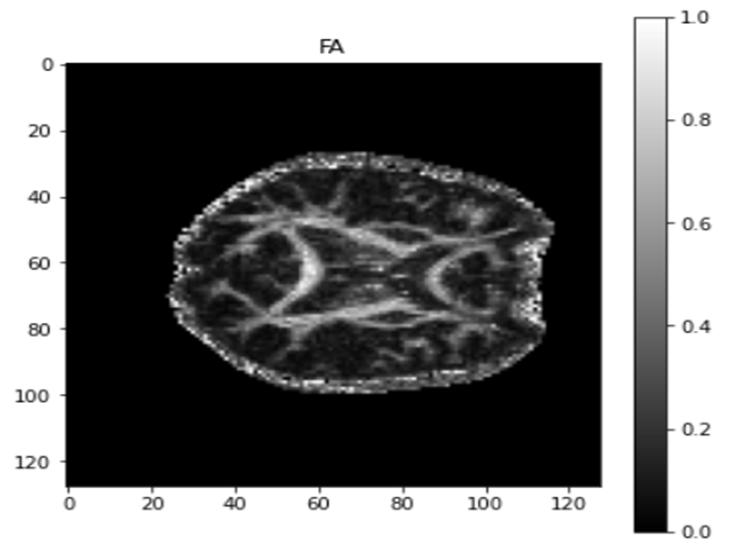

Fractional anisotropy (FA) is a nondirectional proportion ranging from 0 to 1 that is used to express the degree to which diffusion is anisotropic. When it is compared to dense packing, light axonal packing would leave more water in the intercellular spaces; this would result in less restriction of diffusion and, hence, a lower FA. On the other hand, a high degree of myelination would lead axons to be packed together more closely, which would increase FA.

On an anatomical map, the FA of all of the voxels in the brain can be superimposed; voxels with high values are depicted as white, while voxels with low values are represented as black. The FA has been used as the principal measure of white matter integrity in several studies.

FA is formally defined as the normalized variance of the tensor's eigenvalues:

In the case of perfect, isotropic diffusion, the diffusion tensor is a sphere, and FA = 0 (In general FA values vary between 0 and 1). If the starting two eigenvalues are equal then the tensor will be oblate or flat and if the first eigenvalue is greater than the other two, the tensor will have the previously specified ellipsoid shape as diffusion gradually becomes more anisotropic, eigenvalues become more unequal, leading the tensor to grow elongated; with FA approaching, it must be evaluated with caution. It may indicate the density of packed fibres in a voxel and the quantity of myelin around the axons, although it is not always indicative of "tissue integrity."

The subsequent images are the various scalar maps that were generated by making use of the Dipy library. Here, we can see the FA map, which ranges from 0 to 1 and does not take any dimensions into account; it describes the amount of one directional water movement. An FA value of 0 indicates that there is no anisotropy in the movement of water. This is the case for movement that is truly isotropic, such as the movement that one would anticipate in a glass of water or within a collection of cerebrospinal fluid like the ventricular system. An FA value of 1 indicates that water is moving in a single direction only, which is a movement pattern that is typically absent in living things.

Fig. 8 Output FA map